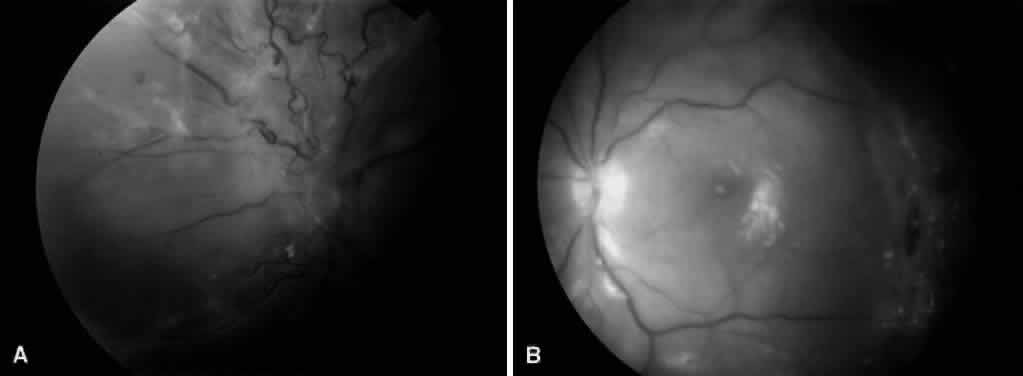

MACULAR TRACTION RETINAL DETACHMENT

Fig. 4. An example of an eye with proliferative diabetic retinopathy and traction retinal detachment involving the macula.

Vitreous traction and contraction of proliferative tissue can produce retinal tears, leading to combined traction-rhegmatogenous detachments. Unlike purely tractional detachments, extramacular rhegmatogenous detachments frequently progress to involve the macula, leading to rapid and severe visual loss. Thus, surgical repair is indicated in combined detachments, whether or not the macula is involved. Often, the retinal breaks are located posterior to the equator, adjacent to areas of fibrovascular proliferation that are under severe vitreoretinal traction. Therefore, this condition is difficult to treat by conventional scleral buckling methods, whereas vitrectomy (with or without scleral buckling) is effective in treating this condition (Fig. 5). Intraocular long-acting gas tamponade is required to treat these detachments. Combined traction-rhegmatogenous detachments have a lower success rate than pure tractional detachments or nonclearing vitreous hemorrhage. In an analysis of 172 eyes that underwent vitrectomy for combined traction-rhegmatogenous diabetic retinal detachment, 48% had an improved visual acuity on final examination.21 A final visual acuity of 20/100 or better was achieved in only 25% of eyes, and a final visual acuity of 5/200 was achieved in 56%. Visual loss progressed to no light perception in 23% (compared with 19% for macular traction detachment and 6% for nonclearing vitreous hemorrhage). Preoperative factors associated with a favorable visual prognosis included visual acuity of 5/200 or better, absence of iris neovascularization, and absence of retinal detachment involving the macula. The only intraoperative factor found to be associated with a favorable visual prognosis was the absence of iatrogenic retinal breaks.

Fig. 5. A. Preoperative fundus photograph of an eye with combined traction-rhegmatogenous retinal detachment from severe proliferative diabetic retinopathy. B. Postoperative fundus photograph of the same eye after vitrectomy, membrane dissection (using delamination technique), and endolaser photocoagulation.

MACULAR EDEMA ASSOCIATED WITH POSTERIOR HYALOIDAL TRACTION

Although the ETDRS showed that focal macular photocoagulation is beneficial in the treatment of clinically significant diabetic macular edema, it has been observed that some patients with diabetic macular edema and a taut, thickened posterior hyaloid do not respond to macular photocoagulation. It has been hypothesized that vitreous traction may cause or exacerbate macular edema in these patients. Lewis and coauthors report the results of pars plana vitrectomy with separation of the posterior hyaloid in 10 eyes with diabetic macular edema and traction associated with a thickened and taut premacular posterior hyaloid.24 Preoperative fluorescein angiography showed a deep, diffuse pattern of leakage in the macula (Fig. 6). Nine of 10 eyes had previous macular photocoagulation, and only 1 of these eyes responded with a temporary decrease in macular edema. Postoperatively, vision improved in nine eyes, and macular edema resolved in eight eyes. Postoperative complications included vitreous hemorrhage, rhegmatogenous retinal detachment, cataract formation, and mild epimacular membrane (each occurring in one eye). Other studies also report visual improvement after vitrectomy and posterior hyaloid separation in such patients.25 Tachi and Ogino report the results of pars plana vitrectomy with separation of the posterior hyaloid in 58 eyes with diffuse diabetic macular edema without posterior vitreous detachment.26 These patients differed from those in prior reports in that they did not manifest a taut, thickened posterior hyaloid, and thus it is not clear whether the posterior hyaloid was responsible for the macular edema. Although these patients showed an improvement in macular edema and visual acuity, this study was not controlled and included only a few patients. Thus, it is reasonable to consider vitrectomy and posterior hyaloid separation in patients with diffuse diabetic macular edema associated with a taut and thickened posterior hyaloid, whereas the long-term efficacy of such surgery in patients with diabetic macular edema without vitreoretinal interface abnormalities has not been conclusively proven.

Fig. 6. A. Fundus photograph of an eye with vitreomacular traction syndrome. B. Fluorescein angiography showing deep, diffuse dye leakage.